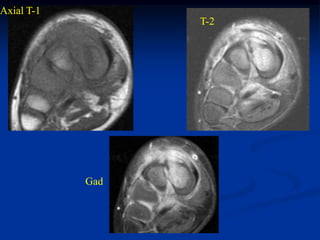

Case #1097

14 year male with

adamantinoma distal

tibia and fibula

Coronal T-1 MRI